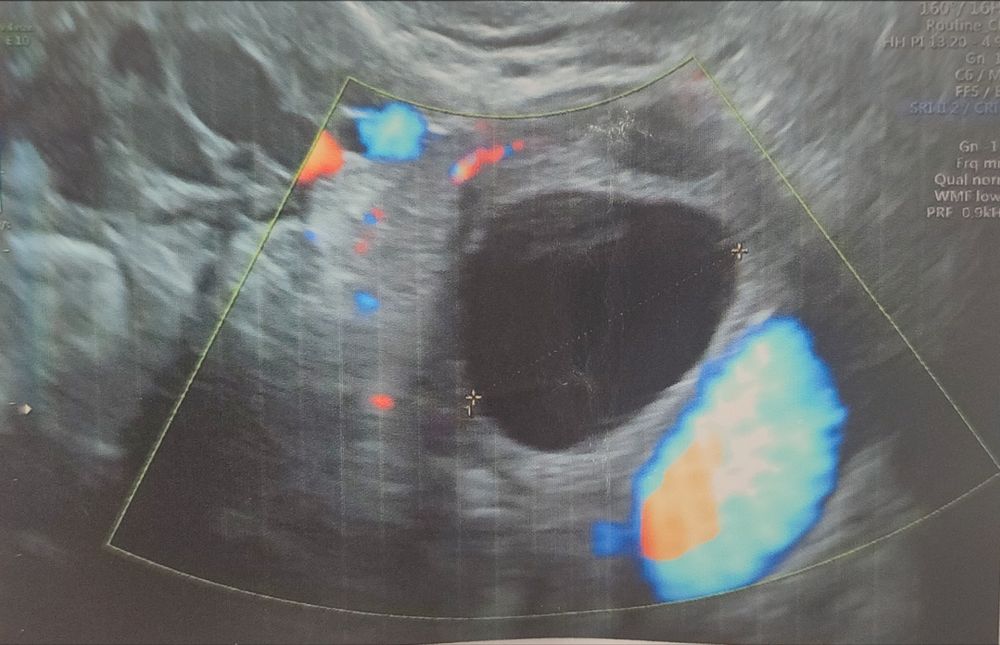

Агата в Зачатие 2 года Фолликул или жт? Фолликулометрия Посмотрите еще 20 записей на эту тему Лучший ответ Виктория Я вижу предовуляторный фолликул. 14.07.2023 Ответить Отменить Ответить Ната Это варч должен был сказать 14.07.2023 Ответить Мой 17 дц❤ Кто прав-врач или окей, гугл? Чаты Беременных Выберите чат: Январята-2026 Февралята-2026 Мартята-2026 Апрелята-2026 Майчата-2026 Июнята-2026 Июлята-2026 Августята-2026